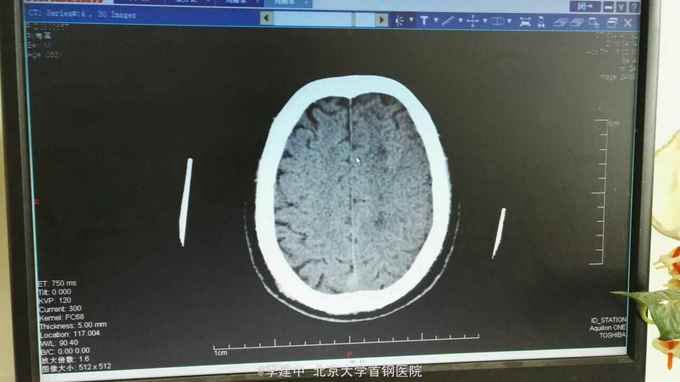

患者,男,63岁,因“ 右侧肢体无力7天,加重4小时”于2016-04-14入院。 既往有高血压病、糖尿病、高脂血症。辅助检查:头CT:多发脑梗死。

诊断:脑梗死 高血压3级 极高危 2型糖尿病 高脂血症 治疗:入院后给予抗血小板聚集、改善脑供血、清除自由基、扩容,脱水及对症支持治疗。2016.4.16接班后查房发现患者呼之无应答。查体:T:37.7℃;P:95次/分;R:20次/分;BP:202/90mmHg。 深度嗜睡至浅昏迷,呼吸节律尚规整,查体不合作。双侧眼球居中,双侧瞳孔不等大,左侧直径3.0mm,右侧直径约1mm。右侧鼻唇沟浅。双侧Babinski'sign、双侧Chaddock'sign(+)。右侧肢体无自主活动。双肺未闻及干湿啰音,心率95次/分,律齐,双下肢无浮肿。急诊复查头CT示:多发脑梗死,左侧额颞顶叶大面积梗死,建议MRI检查进一步明确。阅片可见侧脑室受压明显,中线移位,有脑疝形成。请神经外科急会诊,建议行去骨瓣减压术。告知患者家属上述情况,家属同意转神经外科行急诊去骨瓣减压术。